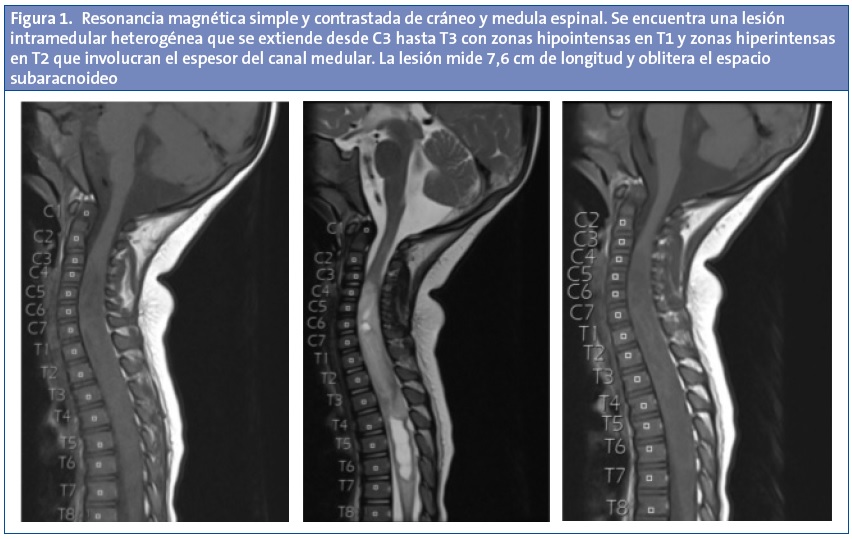

Se solicitan radiografías de columna y cadera, que se reportan como normales y se le solicita una tomografía computarizada (TC) simple de cráneo, sin encontrar datos radiográficos sugestivos del origen de la causa de la sintomatología, razón por la cual se le solicita una resonancia magnética (RM) simple y contrastada de cráneo y médula espinal, encontrándose una lesión intramedular heterogénea que se extiende desde C3 hasta T3 con zonas hipointensas en T1 y zonas hiperintensas en T2 que involucran el espesor del canal medular y la cual mide 7,6 cm de longitud y oblitera el espacio subaracnoideo (Fig. 1).